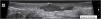

Anechoic fluid collections with echoes (debris) – hypoechoic or anechoic dermal fluid and/or hypodermic sac-like structure connected to the base of the enlarged hair follicle, clinically corresponding to an abscess or fistula (Fig. 7).

- 5.

Hypoechoic fistula/fistulous tracts in the dermis and subcutaneous tissue – dermal or hypodermal hypoechoic or anechoic band-like structure connected to the base of an enlarged hair follicle (Fig. 8).